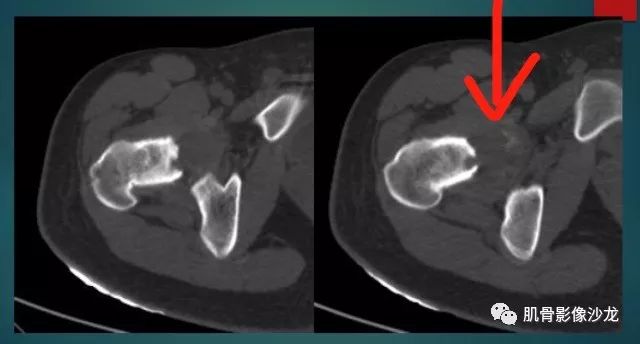

主诉:右髋及右膝部疼痛3月余

现病史:3月前打球时自觉右大腿肌肉拉伤后右髋及右膝部疼痛,自服“活血化瘀”类药物(具体不详)后自觉疼痛缓解,2月前打球时再次扭伤,右髋及右膝部疼痛明显,行走时疼痛加重,自服药物治疗,效果不佳,遂来诊。

医影在线 20:13 干骺端溶骨性破坏,边缘模糊,低密度肿块,似有钙化

Echo 20:13 有骨质破坏,边界不清,有软组织肿块,我觉得恶性是要考虑的

Echo 20:16 软组织肿块突破了骨皮质